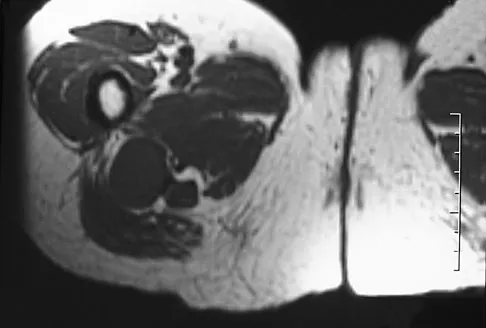

Figures 61a and 61b show the CT and MRI scans of a 40-year-old man who has hip pain. He undergoes total hip arthroplasty and curettage and cementation of the lesion as shown in Figure 61c. Histopathologic photomicrographs of the curettage specimen are shown in Figures 61d and 61e. What is the best course of treatment?

Explanation

The definitive surgery would be removal of the entire resection bed, and in this case of dedifferentiated chondrosarcoma, a hemipelvectomy was performed. The MRI and CT scans show an aggressive cartilage lesion. The histology, representative of a dedifferentiated chondrosarcoma, shows a bimorphic low-grade cartilage lesion with high-grade spindle cell sarcoma. The cartilage lesion is usually an enchondroma or low-grade chondrosarcoma. The dedifferentiated portion is typically a malignant fibrous histocytoma, osteosarcoma, or fibrosarcoma. Weber KL, Pring ME, Sim FH: Treatment and outcome of recurrent pelvic chondrosarcoma. Clin Orthop Relat Res 2002;397:19-28.